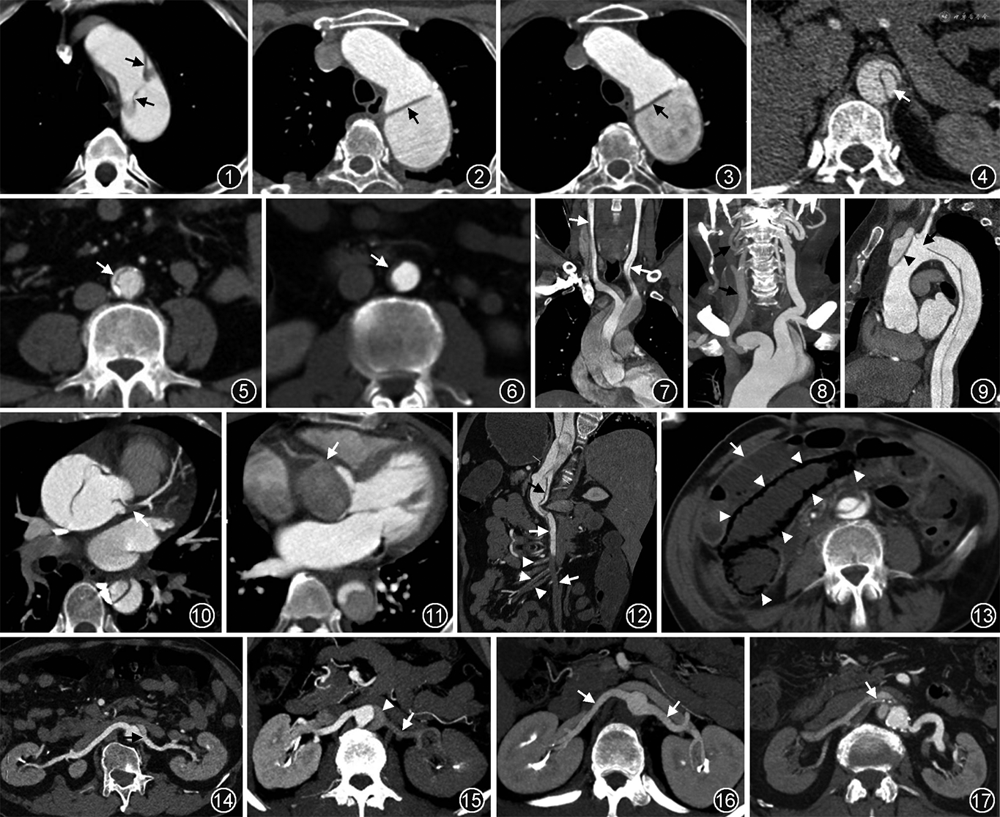

1.内膜片及其撕裂表现——与AD诊断及不良预后相关:在CTA图像的主动脉腔内发现线样低密度结构(内膜片)即可确定AD的诊断。内膜片可能包含钙化斑块。急性期的内膜片薄且在管腔内随血流高度摆动,常因搏动伪影显示较为模糊(图1),有时可引起动态阻塞;随着时间的推移,至亚急性期时内膜片逐步增厚,活动度降低(图2);慢性期的内膜片则厚且固定,重构增加(图3)。内膜片撕裂的程度越严重,横断面图像显示的周长就越长,且周长的增加与不良预后相关。内膜片撕裂严重时甚至可以与中膜完全撕脱分离并堆聚产生套叠,引起远端梗阻或血栓形成[12]。

3.真假腔大小及复杂性——与不良结局相关:真假腔的大小和直径均不相同,需要测量描述。假腔的最大直径可以通过在假腔最大处沿管腔外侧壁向内膜片垂直连线测量获得。真腔几乎总是小于假腔,因为假腔压力高会扩张压迫真腔,可致真腔从轻微受压到完全塌陷甚至闭塞(图4~6)。假腔通常较大,密度低于真腔,内常可见血栓形成。研究显示,在病变进展的过程中,真腔狭窄程度的增加、假腔的扩大及假腔内血栓形成等征象均与不良结局密切相关[14]。此外,A型AD修复术后约75%的患者仍有假腔灌注,其中约一半的患者会出现假腔增大,需在随访中监测。

(1)脑灌注不良(cerebral malperfusion,CM):与B型AD相比,A型AD更容易出现CM。众多的研究结果均显示,CM可能与夹层累及弓上的颈动脉分支密切相关,因此,对于可疑AD且伴有神经症状的患者,建议行头-颈-主动脉联合CTA成像,可为外科提供额外的脑动脉及颈动脉的解剖信息[19]。受累颈动脉及数量、侧别、撕裂的范围及程度、真腔狭窄及闭塞等CTA信息应详细描述,因为这与外科手术中动脉插管的位置选择、扩大颈动脉重建的选择等治疗决策息息相关;而颅内Willis环的先天高变异也是影响A型AD术中脑保护策略的关键。Willis完整或安全变异时,可选择单侧脑保护;Willis环不安全变异时,则可选择双侧脑保护以防止术后脑卒中的发生。我们前期的研究还显示,颈总动脉夹层(图7)、一侧颈总及颈内动脉密度减低(图8)和主动脉弓部破口这3个CTA征象是急性A型AD术后短暂性神经损伤的独立风险预测因子;而升主动脉逆行夹层、主动脉弓部破口则是术后永久性神经损伤的独立危险因素(图9)[20]。此外,也有个案报道将颅脑CT灌注用于AD合并CM患者的评估,可提供更精准的脑灌注不良的功能信息[21]。

(2)冠状动脉灌注不良:主动脉根窦部夹层累及冠状动脉时可引起冠状动脉灌注不良,是急性AD最严重的并发症之一,可导致不可逆的心肌损伤,必须在术中经冠状动脉旁路移植术进行血运重建。冠状动脉灌注不良根据受累的机制分为3种类型[22]:A型,冠状动脉近端开口处撕裂(图10);B型,冠状动脉起自假腔(图11);C型,内膜片环形撕脱,并塌陷套叠,极罕见。值得注意的是,主动脉瓣狭窄是术后出现冠状动脉灌注不良的独立危险因素,CT描述时也需提示。

(3)肠系膜灌注不良:腹主动脉夹层撕裂累及肠系膜上动脉时可致肠系膜、系膜血管及供血的肠管灌注不良(图12,13)。主要症状是腹痛,危及生命的风险是肠坏死和感染性休克。肠系膜上动脉夹层根据影像学特征可分成4型[23]:Ⅰ型,近端和远端均见破口,真假腔相通;Ⅱ型,仅见近端1处破口;Ⅲ型,假腔完全血栓化且伴有溃疡样突起;Ⅳ型,假腔完全血栓化但无溃疡样突起。肠系膜上动脉夹层的真腔狭窄程度可能与灌注不良相关。急性A型或B型AD合并肠系膜灌注不良的发生率分别为14%、7%左右,均与院内死亡密切相关。A型AD合并肠系膜灌注不良的院内死亡率高达60%~75%,预后极差。肠道的缺血或坏死可通过CTA图像中肠壁的强化程度减低或没有强化来明确,但肠坏死极少见。

(4)肾灌注不良:夹层撕裂至腹主动脉时,极易累及肾动脉,致肾灌注不良,CTA表现为肾实质灌注减低或梗死,慢性期可呈现肾萎缩。肾动脉受累根据特点,可分为4型(图14~17)[24]:A型,肾动脉开口附近有内膜片大破口,肾动脉起自真腔或假腔辨别困难;B型,肾动脉完全起自假腔;C型,肾动脉完全起自真腔;D型,肾动脉夹层,管腔内可见撕裂的内膜片。研究显示,肾动脉由假腔供血或真腔狭窄程度大于50%与肾萎缩相关[25]。术前CTA显示一侧或双侧肾皮质灌注减低则是急性AD术后急性肾损伤和死亡的独立危险因素[24]。